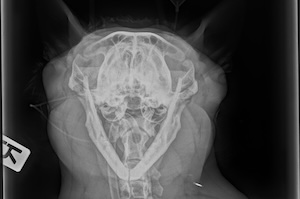

Bildgebende Diagnostik

Digitales Röntgen